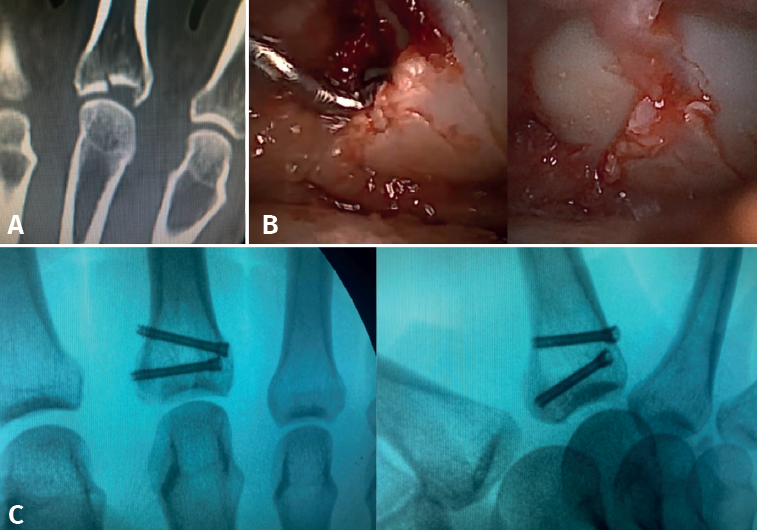

- Fractures with avulsion of the insertion of the collateral ligament (Figures 2 and 3).

- Intra-articular fractures proper, caused by compression or shear mechanisms.

Once the fragments have been reduced, 0.8 or 1.0 Kirschner wires are used to maintain reduction (Figure 7). Sometimes we can only maintain reduction by applying a stop, to prevent the osteochondral fragment from collapsing. Depending on the fracture pattern and the surgeon's preference, we can use conventional screws, cannulated screws, etc. (Figures 8 and 9).